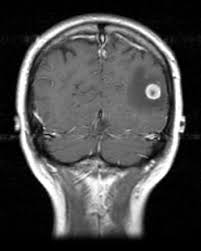

Signs Of Metastatic Breast Cancer In Brain / How Research Is Failing Women With Metastatic Breast Cancer Time : They are usually named after the tissue or organ where the cancer first developed (for example, metastatic lung or breast cancer tumors in the brain, which are the most.. Metastatic brain tumors (also termed secondary brain tumors) are made of cancerous cells that spread through the bloodstream from a tumor located elsewhere in the body. Webmd medical reference reviewed by brunilda nazario. Metastasis is most often found when people report symptoms, such as bone pain, to. Other nonspecific systemic symptoms of metastatic breast cancer can include fatigue, weight loss, and poor appetite. The incidence of brain metastasis from breast cancer (24 % in this review) is increasing due to advances in both imaging technologies leading to earlier detection of the brain metastases and introduction of novel therapies resulting in longer survival from the primary breast cancer.

Metastatic breast cancer means the cancer has spread from your breast to distant organs such as your bones, lungs, or other parts of your body. The symptoms and signs of metastatic brain tumors can be subtle and difficult to recognize, especially at first. Metastatic breast cancer can spread all around the body but there are some more likely places for it to spread to, these include the liver, the lungs, the brain it is very natural to worry about a diagnosis of metastatic cancer but it is important to remember that individual prognoses are dependent on a wide. Metastases from breast cancer can be a frequent finding in routine oncoradiological practice. Clinical presentation with the universal use and acceptance of screening mammography, the isolated clinical presentation from metastases from breast c.

An overview of the presentation, diagnosis. Webmd medical reference reviewed by brunilda nazario. Sometimes people with metastatic breast cancer do not have any of these changes. Metastatic cancer can display general symptoms and symptoms at specific sites of metastasis. Metastatic breast cancer, also referred to as metastases, advanced breast cancer, secondary tumors, secondaries or stage iv breast cancer, is a stage of breast cancer where the breast cancer cells have spread to distant sites beyond the axillary lymph. Signs and symptoms of metastasis. Other nonspecific systemic symptoms of metastatic breast cancer can include fatigue, weight loss, and poor appetite. Metastatic cancer that spreads from its original location is known by the name of the primary cancer. After lung cancer, metastatic breast cancer is the second most common cancer associated with brain metastases in the united states 1. Signs of cancer in the brain include headaches, seizures, vision changes, and dizziness. Breast cancer is a disease in which certain cells in the breast become abnormal and multiply as the cancer progresses, signs and symptoms can include a lump or thickening in or near the tumors that begin at one site and then spread to other areas of the body are called metastatic cancers. They are usually named after the tissue or organ where the cancer first developed (for example, metastatic lung or breast cancer tumors in the brain, which are the most. The cancer has spread to other parts of the body.

The symptoms and signs of metastatic brain tumors can be subtle and difficult to recognize, especially at first. The cancer has spread to other parts of the body. This usually includes the lungs, liver, bones or brain. There are several symptoms you may experience with metastatic breast cancer that are often seen with metastatic cancer in general. After lung cancer, metastatic breast cancer is the second most common cancer associated with brain metastases in the united states 1.

Metastasis is most often found when people report symptoms, such as bone pain, to. Systematic analysis of breast cancer morphology uncovers stromal features associated with survival. Signs and symptoms caused by brain metastases can vary based on the location, size and rate of growth of the metastatic tumors. The incidence of brain metastasis from breast cancer (24 % in this review) is increasing due to advances in both imaging technologies leading to earlier detection of the brain metastases and introduction of novel therapies resulting in longer survival from the primary breast cancer. For example, cancer that has spread from the breast to the brain. What you experience usually relates to where the tumor is and its size. Metastatic cancer can display general symptoms and symptoms at specific sites of metastasis. We often find these tumors when testing for other conditions or when investigating the stage of your primary cancer. Learn about them and when to talk to your doctor. Signs and symptoms of metastasis. Groaning, grimacing, or appearing restless could be signs that a. Webmd medical reference reviewed by brunilda nazario. (redirected from stage iv breast cancer).